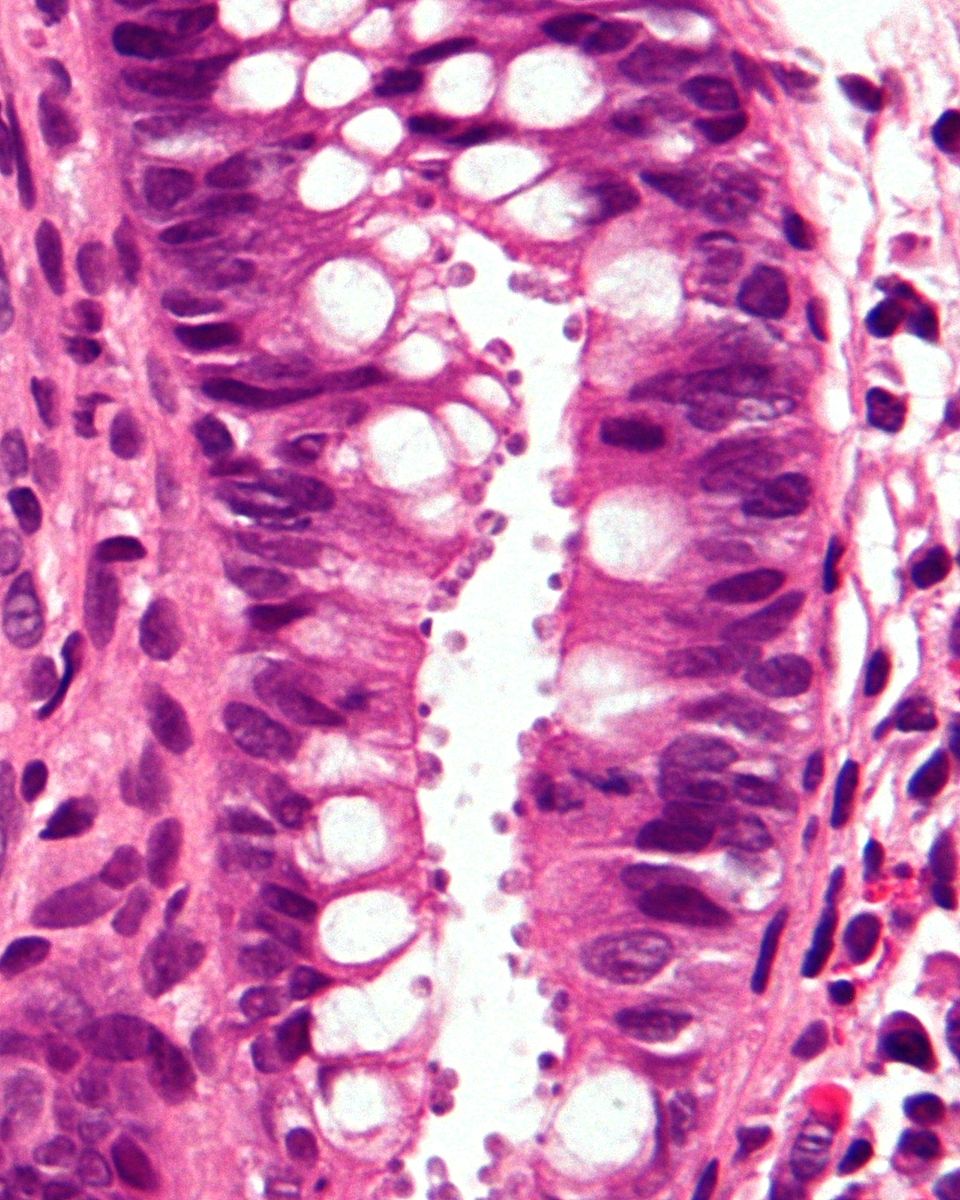

Kryptosporidióza (skrátene "krypto") je parazitická choroba spôsoboná prvokom Cryptosporidium z kmeňa Apicomplexa. Postihuje črevá a typicky je to akútná krátko trvajúca infekcia. Šíri sa fekálno-orálnou cestou, často kontaminovanou vodou. Hlavný symptóm je hnačka, ktorá u ľudí s neporušeným imunitným systémom sama skončí. U ostatných ako napríklad pacientov AIDS sú symptómy vážnejšie a často fatálne.